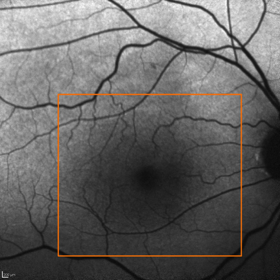

Dazu drei Beispiele anhand einer Autofluoreszenz-Laser-Aufnahme. Alle drei Patienten haben eine Sehschärfe (Visus) von 0,5 (fälschlicherweise oft im Jargon als "50%" bezeichnet). Das bedeutet, daß alle drei 2 Punkte erst als 2 Punkte sehen, wenn diese 2 Winkelminuten voneinander entfernt sind (oder erst wenn sie halb so weit von einem Objekt sind wie ein Augengesunder mit einem Visus von 1,0).

Normale gesunde Makula.